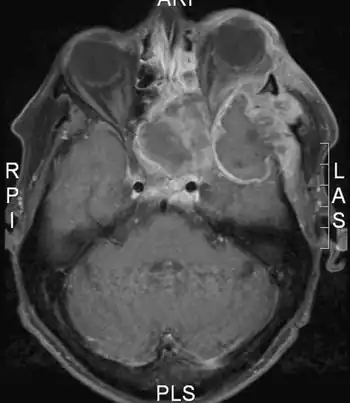

Image shows huge plasmablastic lymphoma infiltrating the left orbit